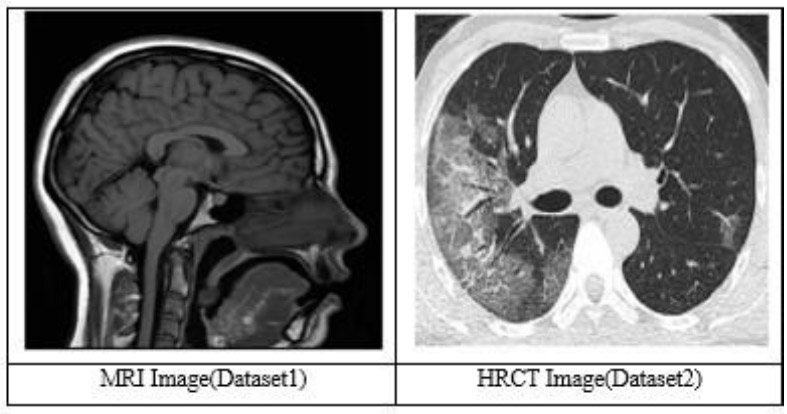

3.1.1. MR Image

Based on the image characteristics, the present scan is most likely to be identified as a T1-weighted MRI sequence. The T1-weighted image also shows that the gray substance of the brain is darker than the white substance, and the cerebrospinal fluid within the ventricle also appears dark. This sequence is mainly applied to high-resolution anatomical imaging to produce clear boundary demarcation between various structures of the brain and is well employed in the architectural variability of the human brain [62].

3.1.2. HRCT

According to the image characteristics, this scan is probably a High-Resolution Computed Tomography (HRCT) of the chest. In HRCT imaging, lung tissue is imaged in a thin slice thickness of 1-2 mm, which enables excellent depiction of lung structures and minimal parenchymal modifications. Its late phase is preferable for evaluating lung diseases, as it provides excellent resolution and contrast [62].

Fig. (3) demonstrates the dataset images. It shows two images, MRI and HRCT.

Dataset (MRI & HRCT image) [62].